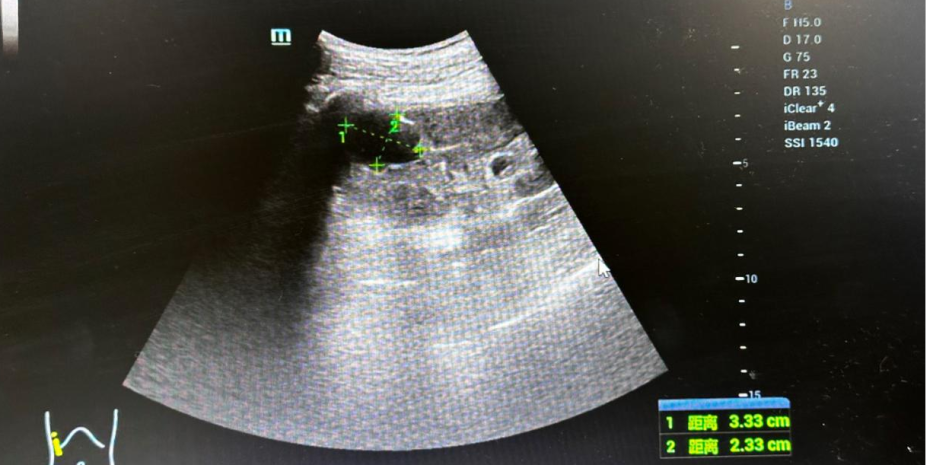

患者,男,73岁,发现双肾囊肿半年余,患者半年前体检发现泌尿系彩超,双肾囊肿,左肾囊肿大小6.4✖4.5✖5.5cm,2024年6月4日就诊我科门诊复查泌尿系彩超示:双肾囊肿,左肾囊肿大小7.2✖6.0✖5.5cm。2024年6月18日为行肾囊肿穿刺引流硬化治疗入院。初步诊断:双肾单纯性肾囊肿。

手术时引流前超声图片